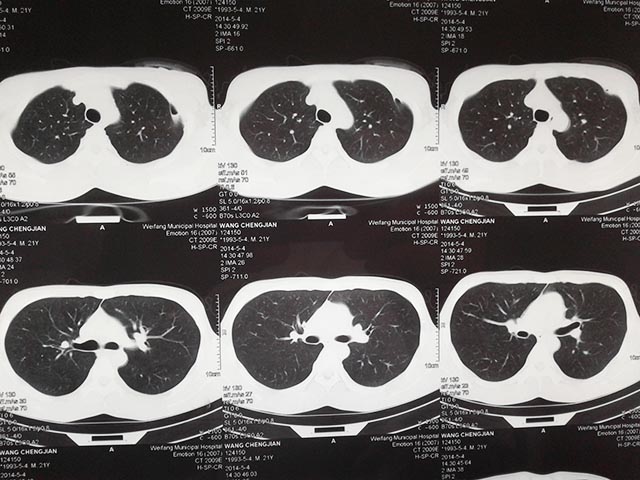

肺大皰自發(fā)性氣胸手術(shù)后